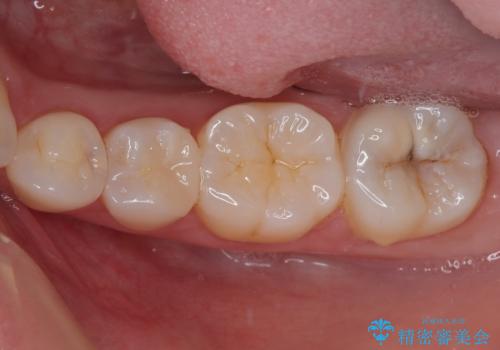

セラミックインレーの装着時には、唾液の侵入を防ぐために、ラバーダム防湿を行いました。

見た目、機能面共に大変喜んでいただきました。